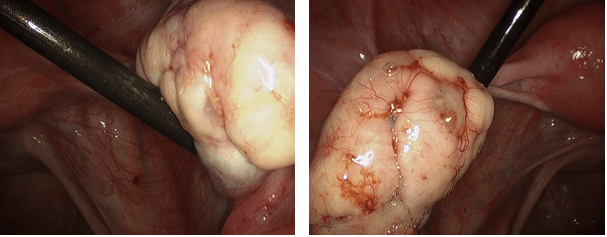

The photos below show several different types of ovarian masses:

These two photos show implants of a serious Low Malignant Potential (LMP) tumor on the surface of both the right and left ovaries. The tumor implants are clear to reddish glandular spots on the ovarian surfaces. Those on the surface of the left ovary (left photo) demonstrate very small, fine capillaries (blood vessels) growing away from the tumor implants.